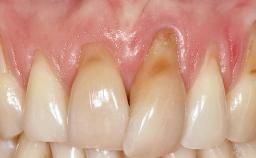

A 30-year-old woman was referred by her general dentist for evaluation of an esthetic complication related to previous implant treatment for congenitally missing maxillary lateral incisors. The patient’s chief complaint was the inadequate esthetic appearance of her smile. The case demonstrates the use of a combined approach to achieve optimal results. Two different flap designs - a tunnel technique and a coronally advanced flap - are employed based on the surgical objectives for the affected site.

Soft Tissue Grafting Yes